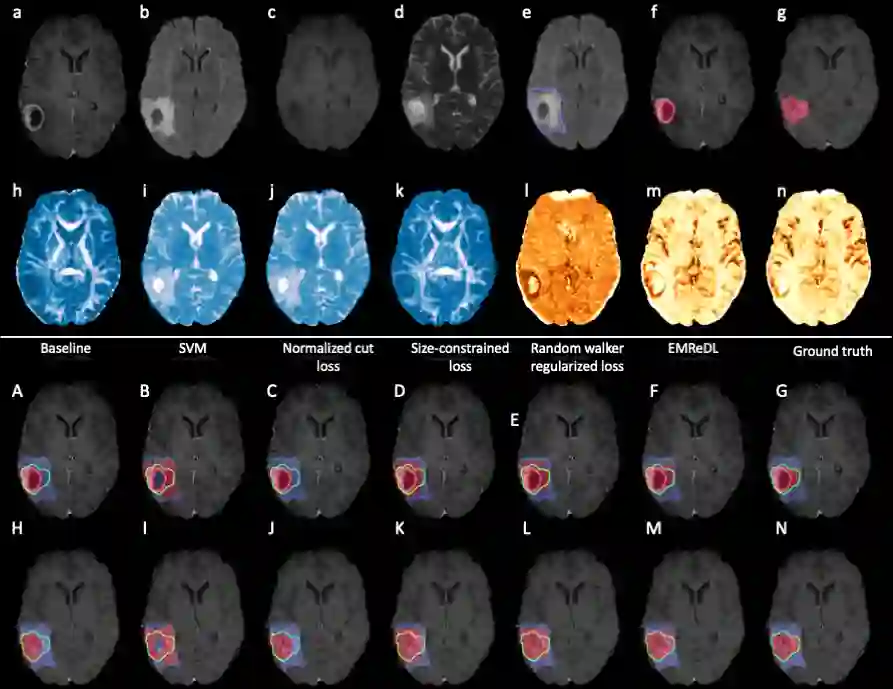

We present an Expectation-Maximization (EM) Regularized Deep Learning (EMReDL) model for the weakly supervised tumor segmentation. The proposed framework was tailored to glioblastoma, a type of malignant tumor characterized by its diffuse infiltration into the surrounding brain tissue, which poses significant challenge to treatment target and tumor burden estimation based on conventional structural MRI. Although physiological MRI can provide more specific information regarding tumor infiltration, the relatively low resolution hinders a precise full annotation. This has motivated us to develop a weakly supervised deep learning solution that exploits the partial labelled tumor regions. EMReDL contains two components: a physiological prior prediction model and EM-regularized segmentation model. The physiological prior prediction model exploits the physiological MRI by training a classifier to generate a physiological prior map. This map was passed to the segmentation model for regularization using the EM algorithm. We evaluated the model on a glioblastoma dataset with the available pre-operative multiparametric MRI and recurrence MRI. EMReDL was shown to effectively segment the infiltrated tumor from the partially labelled region of potential infiltration. The segmented core and infiltrated tumor showed high consistency with the tumor burden labelled by experts. The performance comparison showed that EMReDL achieved higher accuracy than published state-of-the-art models. On MR spectroscopy, the segmented region showed more aggressive features than other partial labelled region. The proposed model can be generalized to other segmentation tasks with partial labels, with the CNN architecture flexible in the framework.